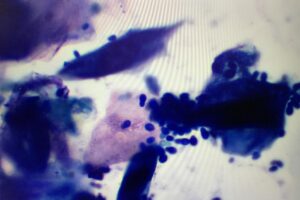

消化器症状は、動物病院に来院する原因としては比較的良くみることができます